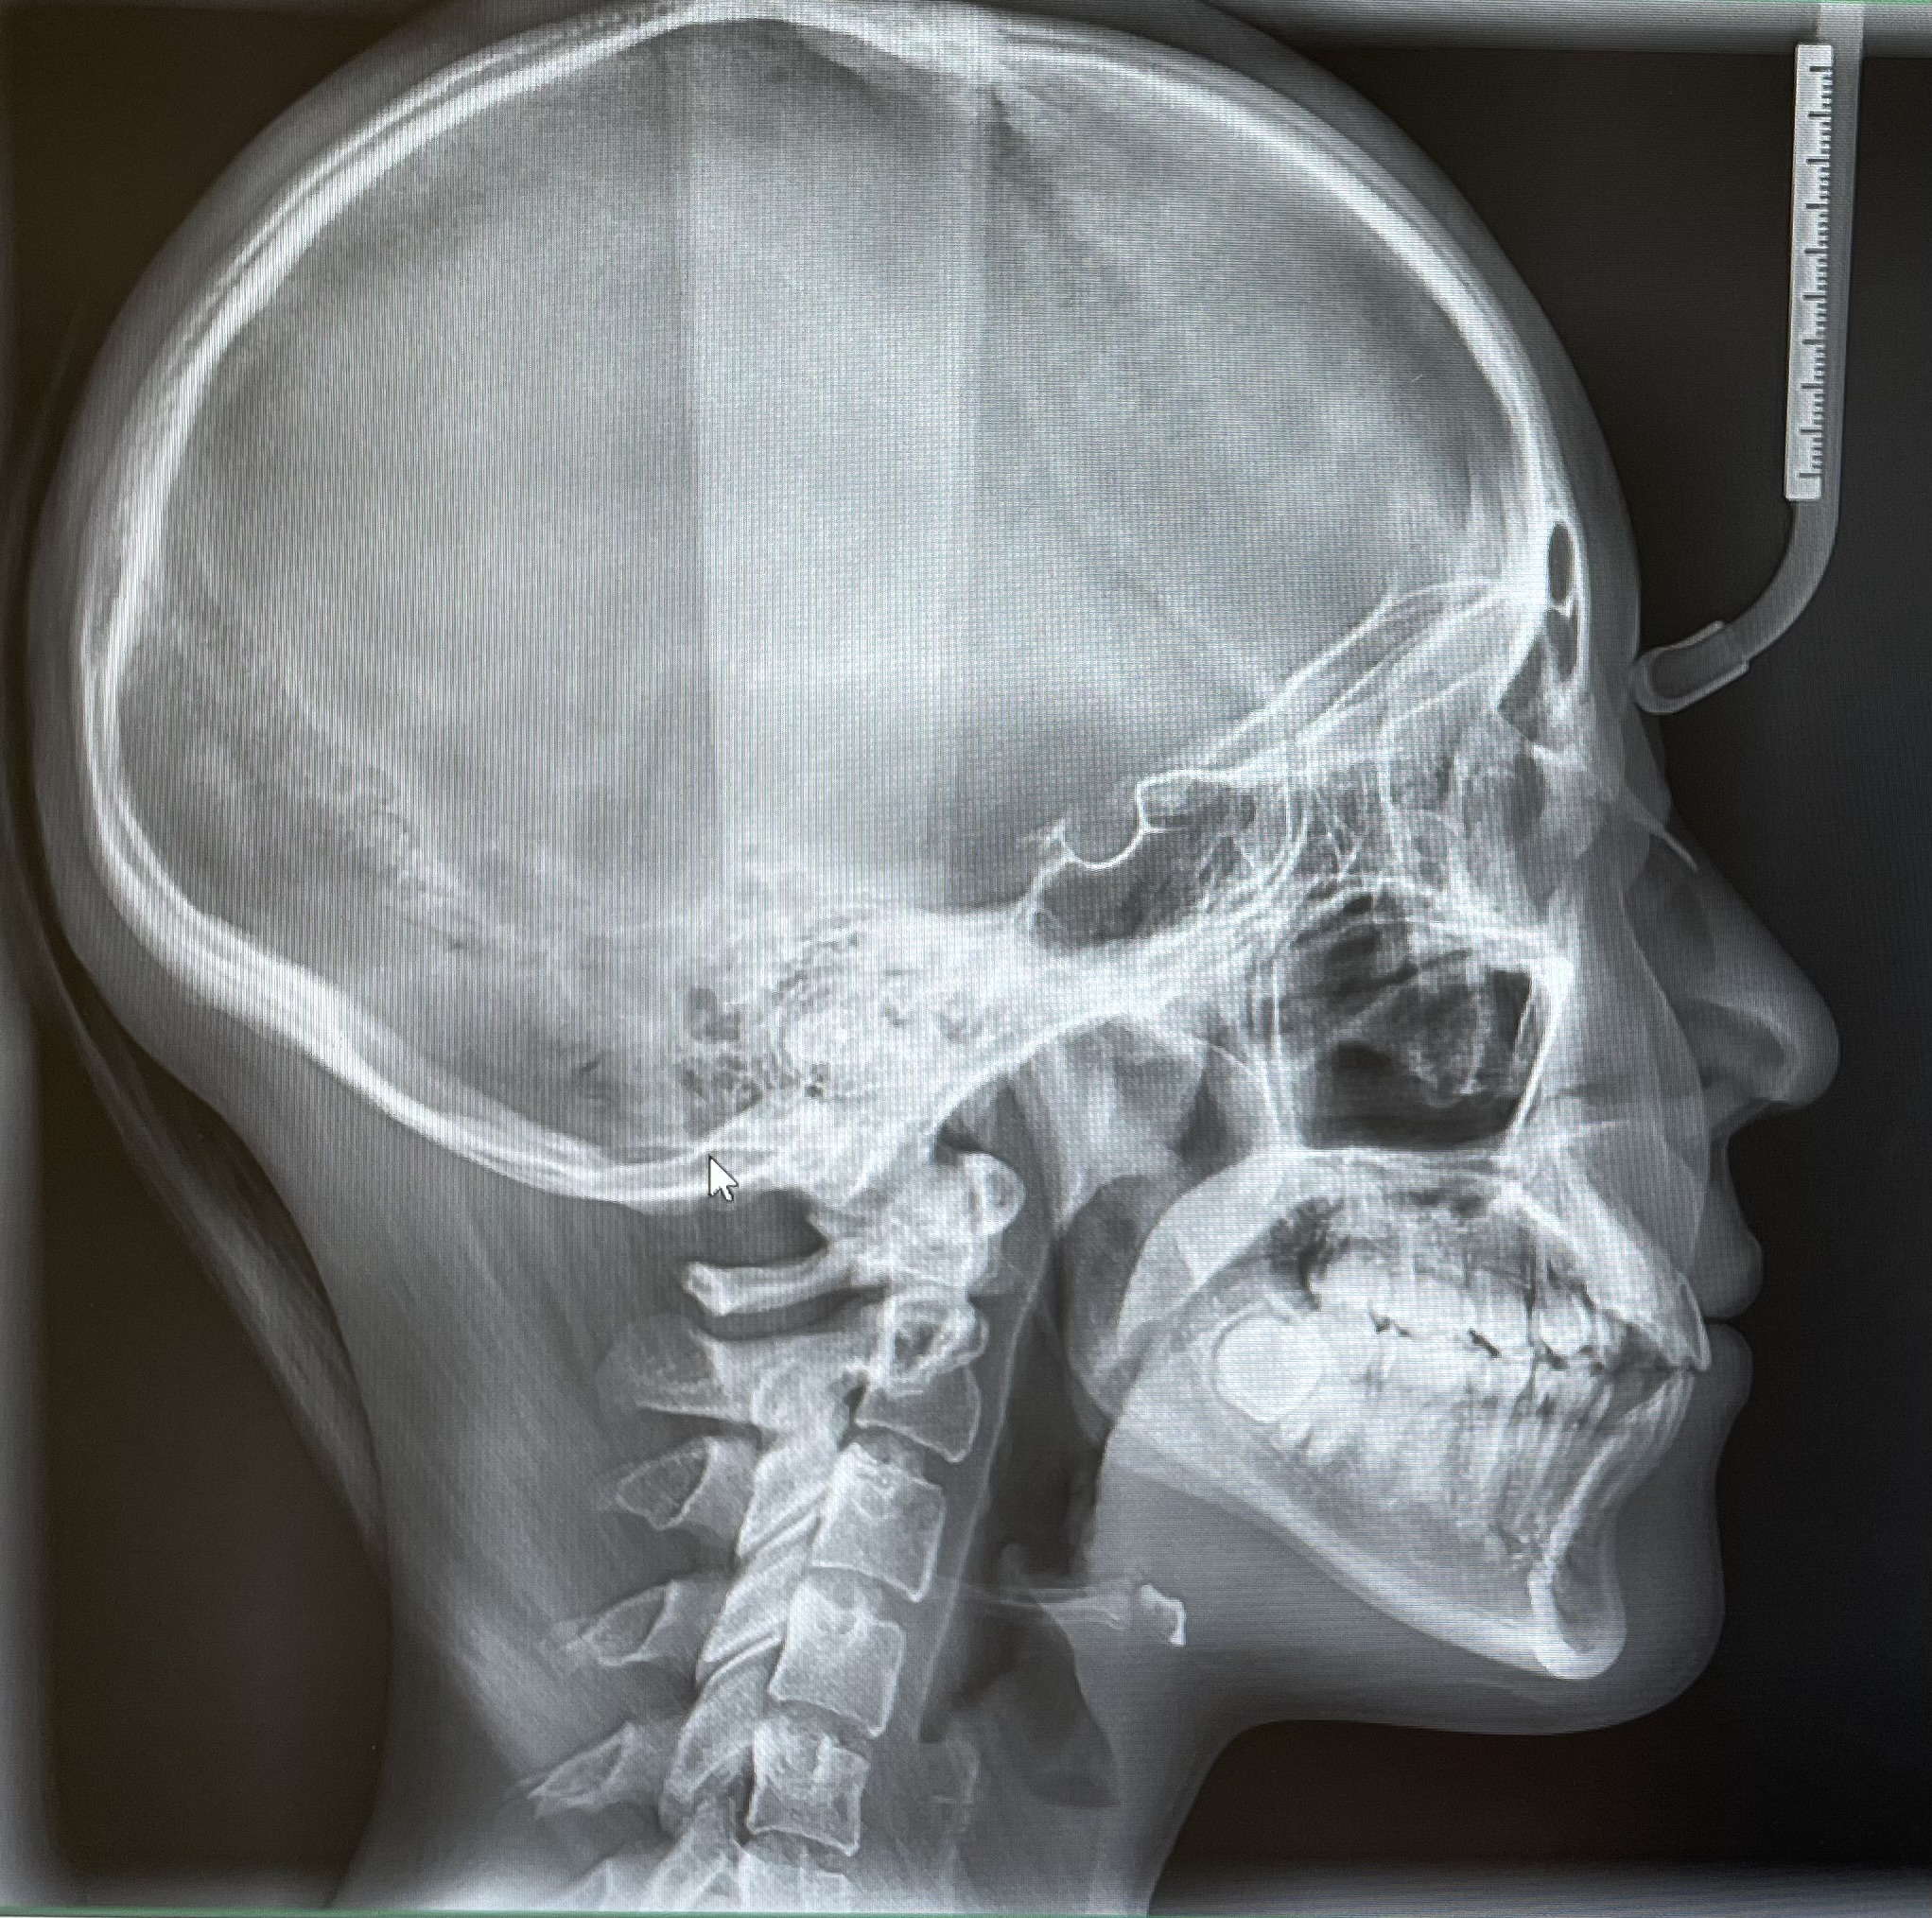

セファロ写真の重要性(矯正歯科)

矯正治療では、通常のレントゲンだけでなくセファロ(頭部X線規格写真)を撮影することがとても大切です。

セファロは、頭部を一定の位置に固定して横顔や正面から撮影することで、

顎の骨格や上下のバランス、歯の傾きなどを正確に評価できます。

セファロでわかること

・上顎と下顎の前後・垂直的な位置関係

・骨格的な出っ歯・受け口・開咬などの程度

・歯の傾きや前突量(どれだけ前に出ているか)

・顔面全体のバランス(Eライン、横顔の美しさ)

・成長期のお子さまの顎の成長方向

セファロ分析により、どのくらい歯を動かすか、抜歯が必要か、骨格的に手術を伴うべきかといった判断が科学的にできます。

治療前後の写真を比較することで、歯や骨格の変化を客観的に評価できるのも大きなメリットです。